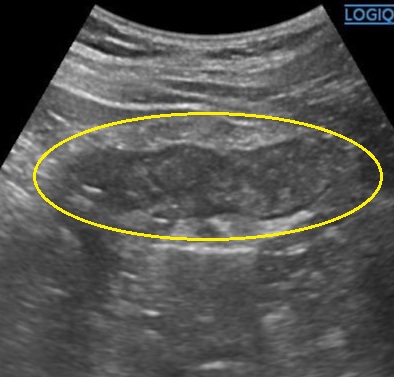

- エコー検査で下行結腸(左側の大腸)に璧肥厚あり、周囲に炎症あり。

通常急性期に内視鏡は不要なことがほとんどです。症状改善後に大腸がんや炎症性腸疾患の除外の為に内視鏡をお勧めします。 - CT・エコー:腸管壁肥厚、脂肪織濃度上昇、虚血範囲の確認

虚血性大腸炎の超音波(エコー)画像